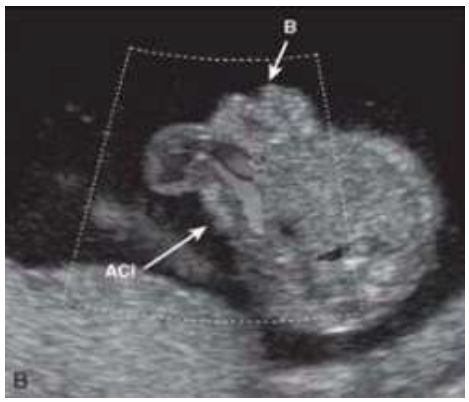

Em relação a malformação da parede abdominal e do trato gastrointestinal fetal, assinale a alternativa correta: